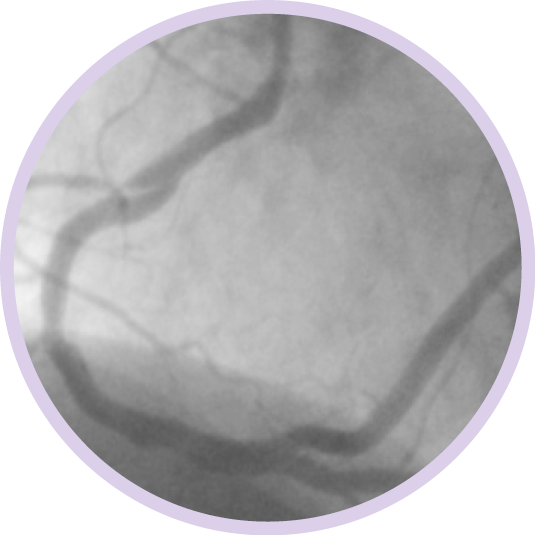

Ангиография дает сведения о характеристиках просвета сосуда, но не позволяет получить четкого изображения сосуда и поражения.

Между тем, использование ВСУЗИ помогает получить более четкую картину и улучшить результаты лечения пациента за счет планирования стентирования на основе данных и оптимизации стента после его установки1.